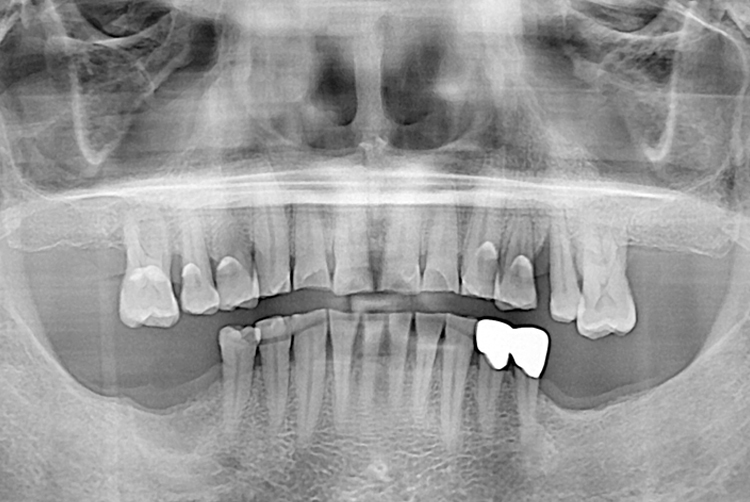

[임플란트] 임플란트

치료후 : 2019-11-29

세종치과는 많은 환자와 다양한 케이스를 바탕으로 항상 편안한 임플란트 수술을 제공하고자 노력하고,

오래동안 튼튼히 쓸 수 있는 임플란트 수술을 가장 큰 목표로 삼고 있습니다